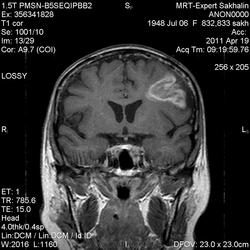

склоняюсь к кровизлиянию в левой теменной долей, начало перехода острой стадии в раннюю подострую( по периферии определяется повышение МРС по Т1 ВИ -метгемоглобин). Справа -старые кортикальные постишемческие глиозно-атрофические изменения. Контрастируется , вероятно за счет формирования участков ангионеогенза.

А мне кажентся больше за опухоль. Может быть сосудистая мальформация. Клинико-анамнестические данные есть?

Это демиелинизирующий процесс, острая стадия, причем с геморрагическим пропитыванием в центре пораженных участков. В принципе, соответствует тяжелому рассеяному склерозу, хотя может быть и геморрагическая форма ОДЭМ. Также могут быть мозговые проявления системного васкулита: надо знать анамнез.

На фоне ДЭП изменений МР-картина ОНМК по ишемическому типу в бассейне ЛСМА с участками геморрагического пропитывания. Аналогичный участок но в более поздней фазе в задних конвнкситальных отделах правой теменной доли.

О.С., я согласен, что контрастирование нехарактерно для ОНМК, ведь в подострую стадию инфаркта наблюдается, как правило, гиральный тип усиления. Плюс, на ОНМК непохоже то, что поражено почти только белое вещество, а кора интактна. И потом, при такой локализации инфаркта обязательно должна быть яркая клиника, и уж никак не только "головная боль".

Что касается снимочков мне кажется что зона патологического сигнала в левой гемисфере можно расценить как подострую стадию ОНМК с геморрагическим пропитыванием, справа как последствия ОНМК. При чем множественные очаги скорей всего как проявление ХМНК. И обязательно рекомендовать контрольное МРТ в динамике . Если это действительно ОНМК на фоне лечения отек уйдет и будет формированиться зона кистозно-глиозных изменений, а если отек будет нарастать значит надо думать о объемном процессе.

ОНМК по геморрагическому типу, почти классика.